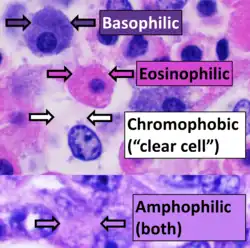

H&E is the combination of two histological stains: hematoxylin and eosin. The hematoxylin stains cell nuclei a purplish blue, and eosin stains the extracellular matrix and cytoplasm pink, with other structures taking on different shades, hues, and combinations of these colors.[5][6] Hence a pathologist can easily differentiate between the nuclear and cytoplasmic parts of a cell, and additionally, the overall patterns of coloration from the stain show the general layout and distribution of cells and provides a general overview of a tissue sample's structure.[7] Thus, pattern recognition, both by expert humans themselves and by software that aids those experts (in digital pathology), provides histologic information.

Hematoxylin principally colors the nuclei of cells blue or dark-purple,[6][15][14] along with a few other tissues, such as keratohyalin granules and calcified material. Eosin stains the cytoplasm and some other structures including extracellular matrix such as collagen[5][7][14] in up to five shades of pink.[8] The eosinophilic (substances that are stained by eosin)[5] structures are generally composed of intracellular or extracellular proteins. The Lewy bodies and Mallory bodies are examples of eosinophilic structures. Most of the cytoplasm is eosinophilic and is rendered pink.[10][15] Red blood cells are stained intensely red.

The structures do not have to be acidic or basic to be called basophilic and eosinophilic; the terminology is based on the affinity of cellular components for the dyes. Other colors, e.g. yellow and brown, can be present in the sample; they are caused by intrinsic pigments such as melanin. Basal laminae need to be stained by PAS stain or some silver stains, if they have to be well visible. Reticular fibers also require silver stain. Hydrophobic structures also tend to remain clear; these are usually rich in fats, e.g. adipocytes, myelin around neuron axons, and Golgi apparatus membranes.